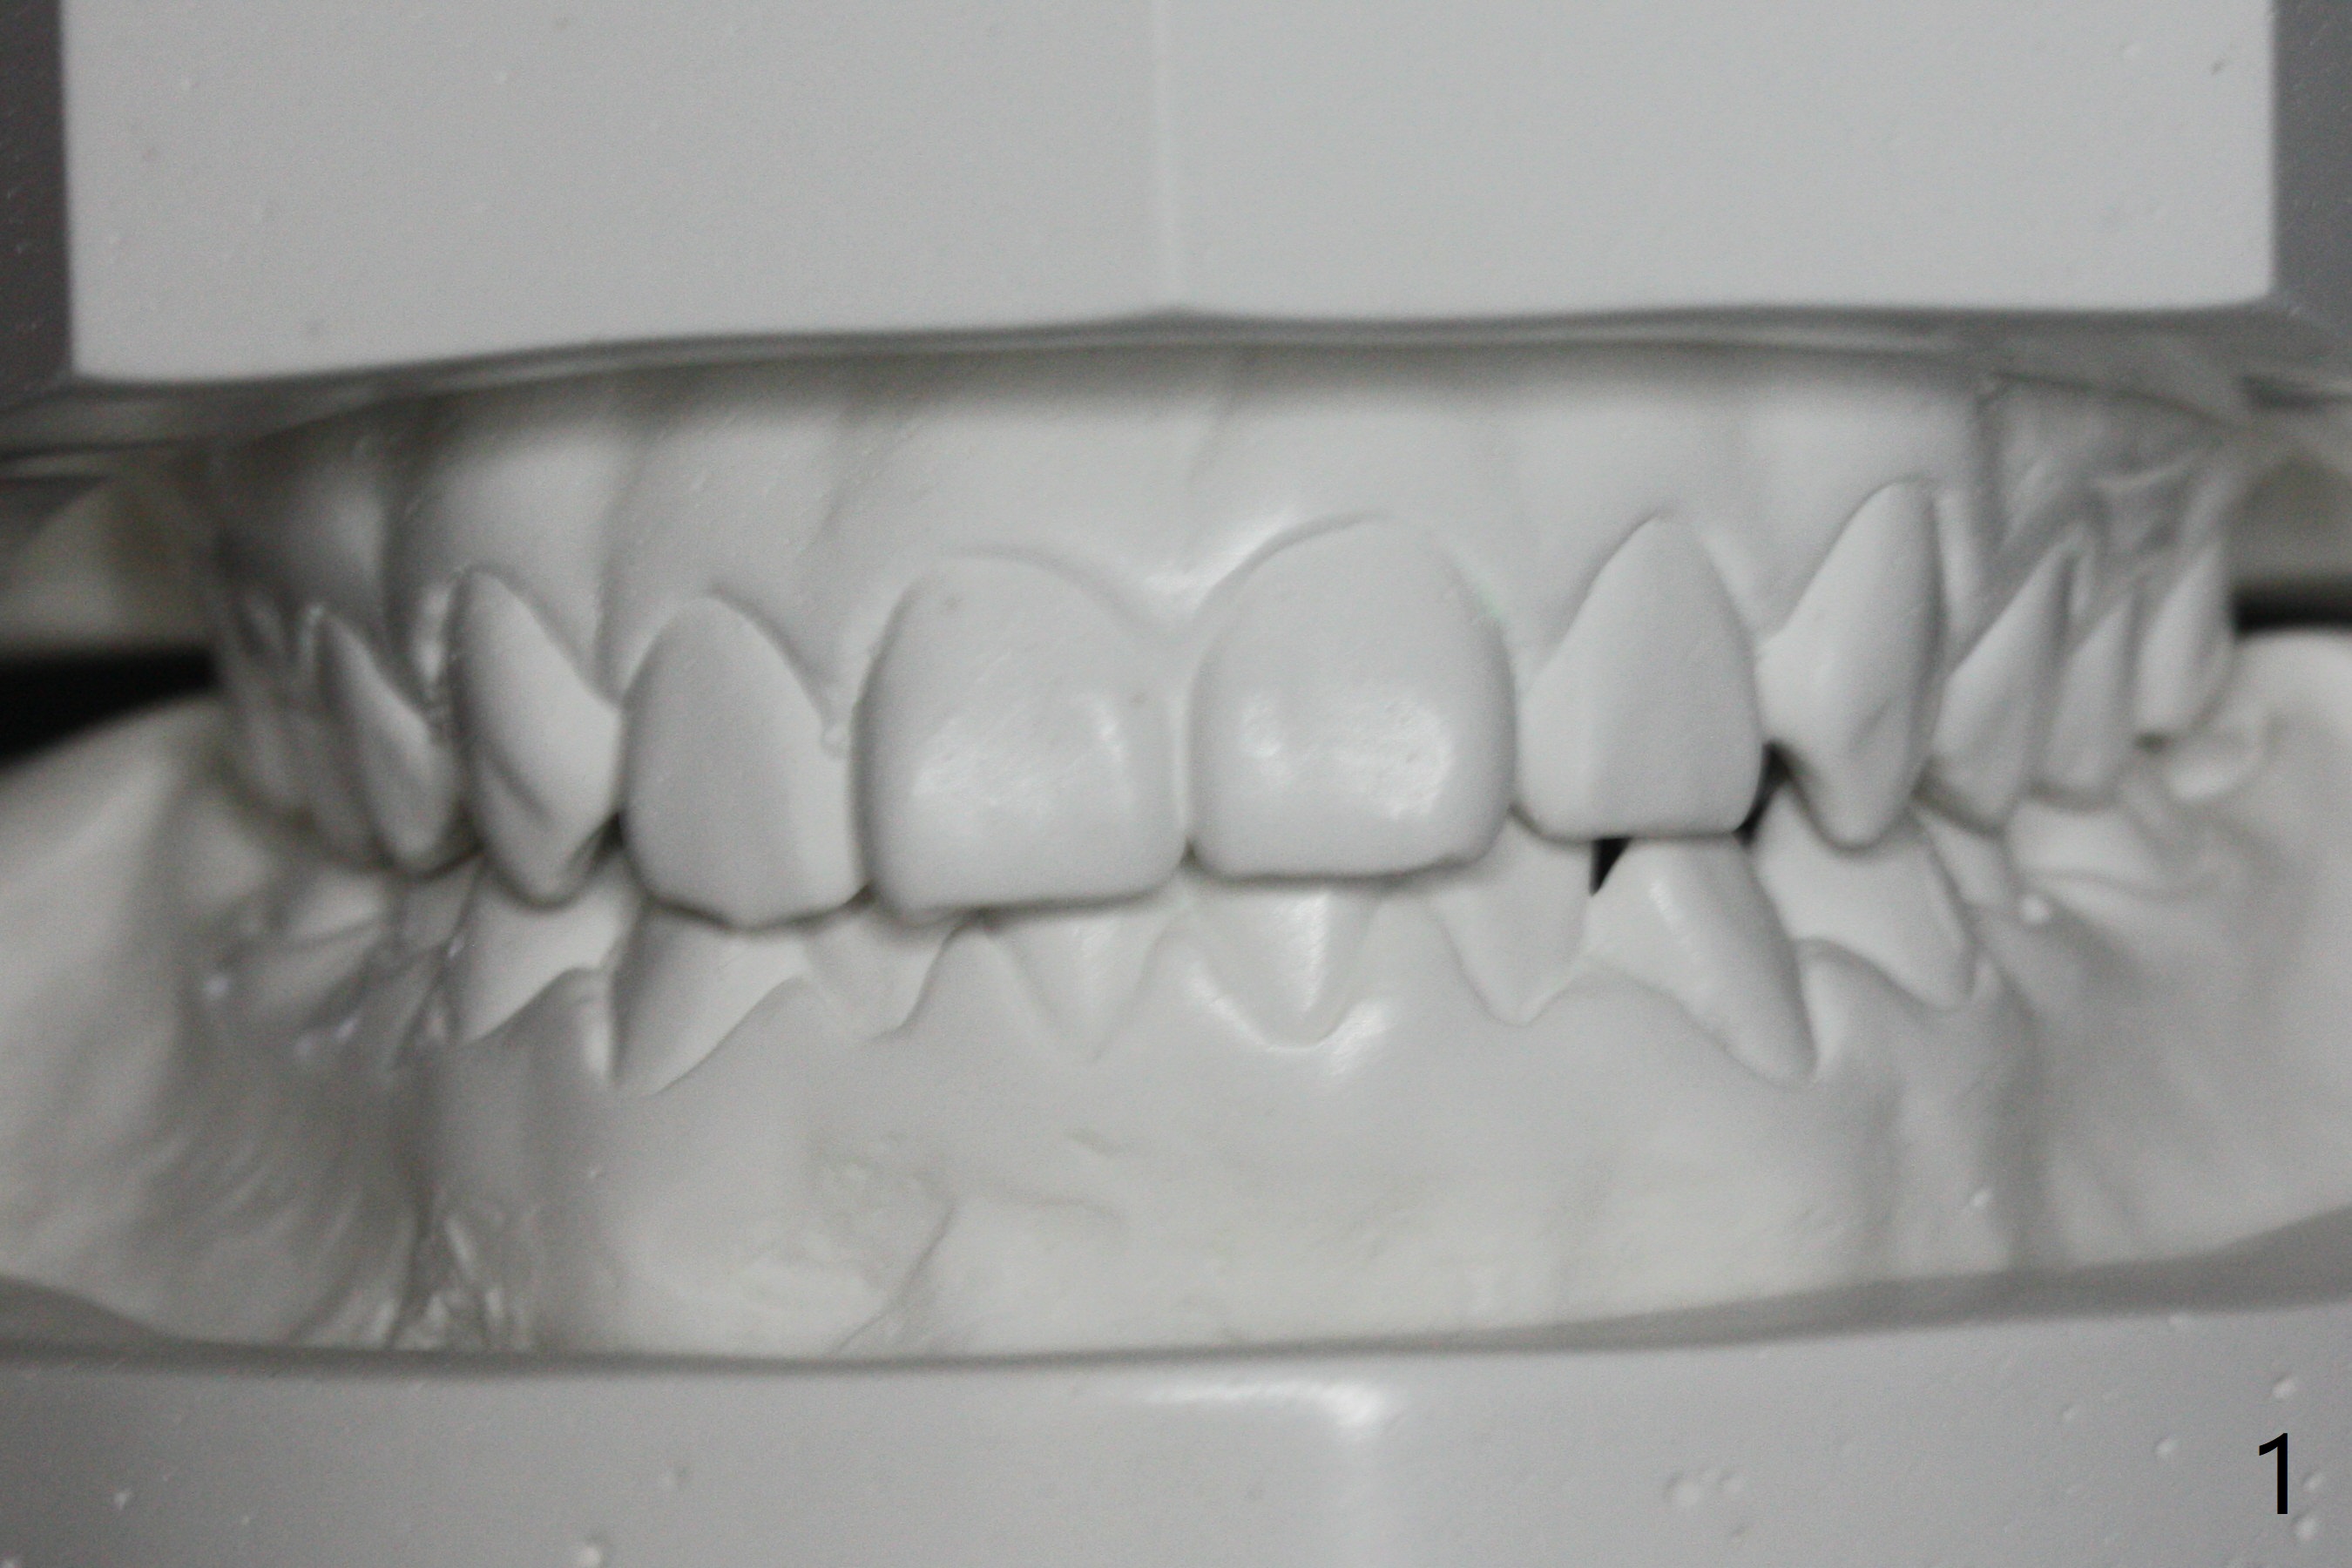

Relapse

A 11-year-old man starts orthodontic treatment and finishes in 9 months. Two years later crowding relapses because of loss of suck down retainers. It appears that lingual retainer is necessary.